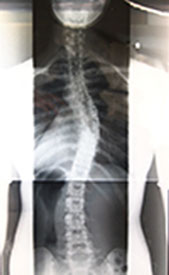

私、杉山陽子自身、この脊柱側彎症(構築性脊柱側彎)が小学校5年次の学校検診で発覚し、以後進行を続け成人に至りました。

上記の写真は私自身のレントゲン写真です。

以後、改善の為にいろいろな取り組みを行ってきた経緯がありますが、2009年より本格的に、側彎症の為にピラティスを実践したことで、発症以来はじめて明らかな改善が見られました。